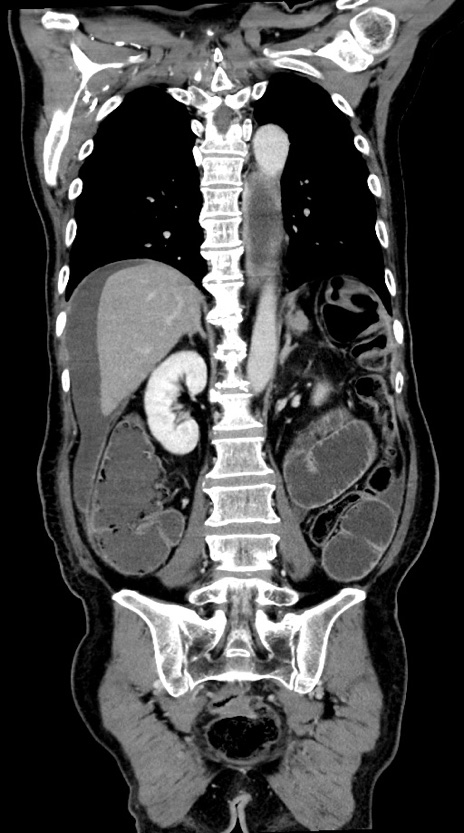

横断像

【症例】60歳代男性

【主訴】嘔吐

【現病歴】胃癌にて胃全摘後。食思不振が悪化し、夜中に嘔吐することがある。

【既往歴】胃癌、胃全摘、脾摘、胆摘後

【データ】WBC 5900、CRP 10.56